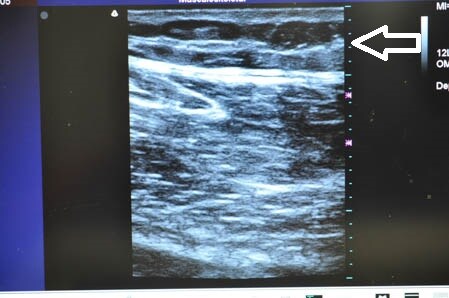

最後に参考までに今回の患者様の

硬膜外麻酔(患者様はこれをたくさんインスタでご覧になったそうです)と

術中の模様を紹介しましょう。